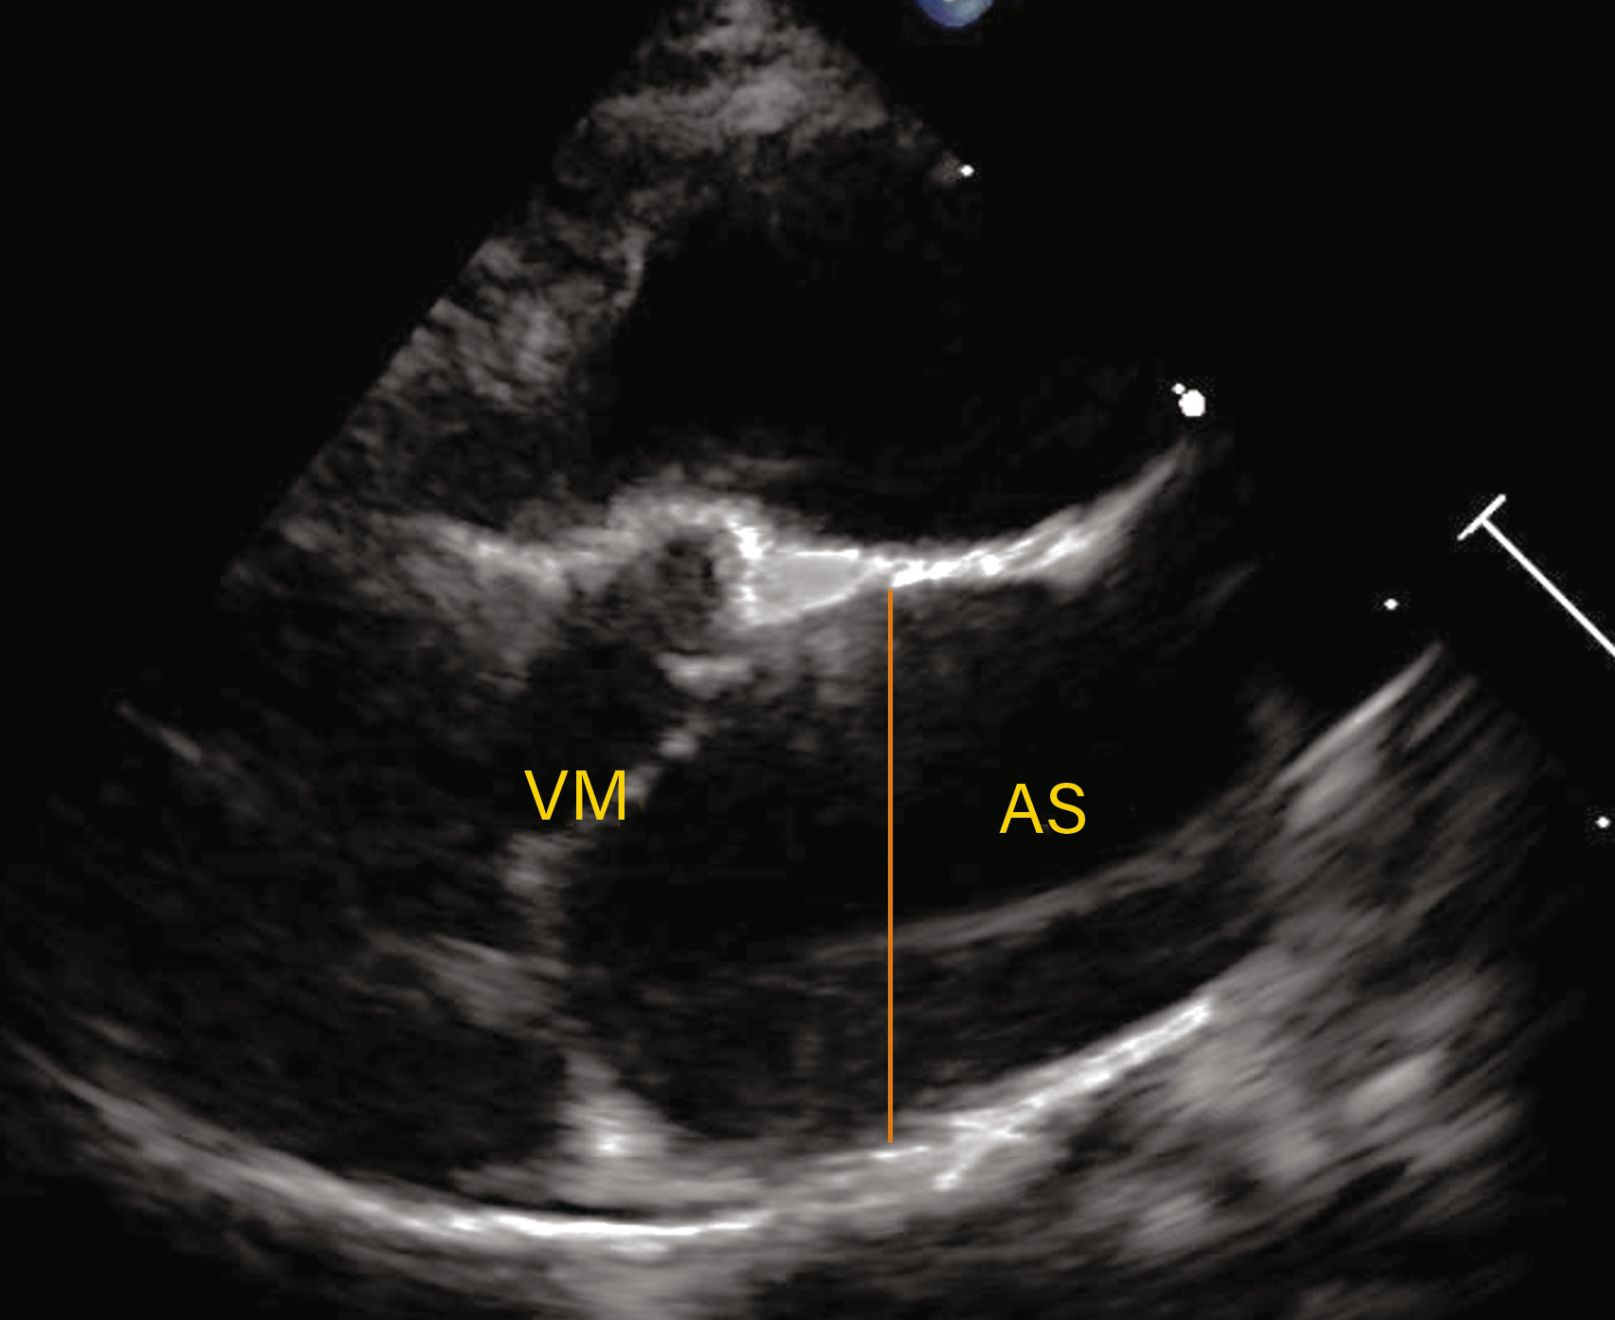

Vizualizare parasternală dreaptă în ax lung cu 4 camere prezentând hipertrofia simetrică a septului interventricular și a peretelui liber al ventriculului stâng.

Figura 2c. Observațiile ecocardiografice ale HCM pot să prezinte o mare variabilitate. Vizualizare parasternală dreaptă în ax lung cu 4 camere prezentând hipertrofia simetrică a septului interventricular și a peretelui liber al ventriculului stâng.

Credit: Catheryn Partington Joanna Dukes-McEwan

Abrevieri: LA , atriul stâng (AS); LV, ventriculul stâng (VS); Pm, mușchiul papilar

Abrevieri: Ao, aorta; IVS (SIV), sept interventricular; LA, atriul stâng (AS); LV, ventriculul stâng (VS); LVFW, peretele liber al ventriculului stâng; MV, valva mitrală (VM).